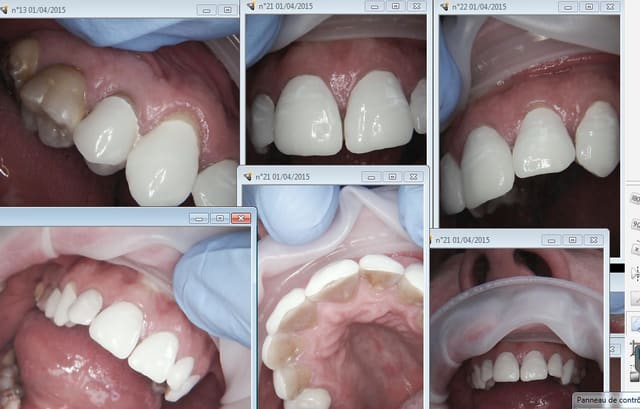

J'ai 300 ( environ) éléments cerecs à mon actif sur 2 ans, après j'ai arrêté de faire mumuse. -)))))

L'empreinte optique je connais un peu. Je suis convaincu de son avenir, mais je laisse les autres se casser le nez dessus le temps que la technologie se stabilise, chacun son tour. -)))))

Ceux là ont 8 ans.

Capture d e cran 2015 04 01 01.12 - Eugenol

Capture d e cran 2015 04 01 01.17 - Eugenol

Tiens un autre de mes exploits cerec. Nom de dieu que c'est moche, choix du patient 1M1 et encore j'ai réussi a éviter le 0M1 ( barre à blanc lavabo toutes because traumatisé par la teinte tétracyclines) Ca a 9 ans, il est ravi !-))))))

RDV one shot de 14 h à 21 h, je ne le conseillerais pas meme à mon pire ennemi.-)))))